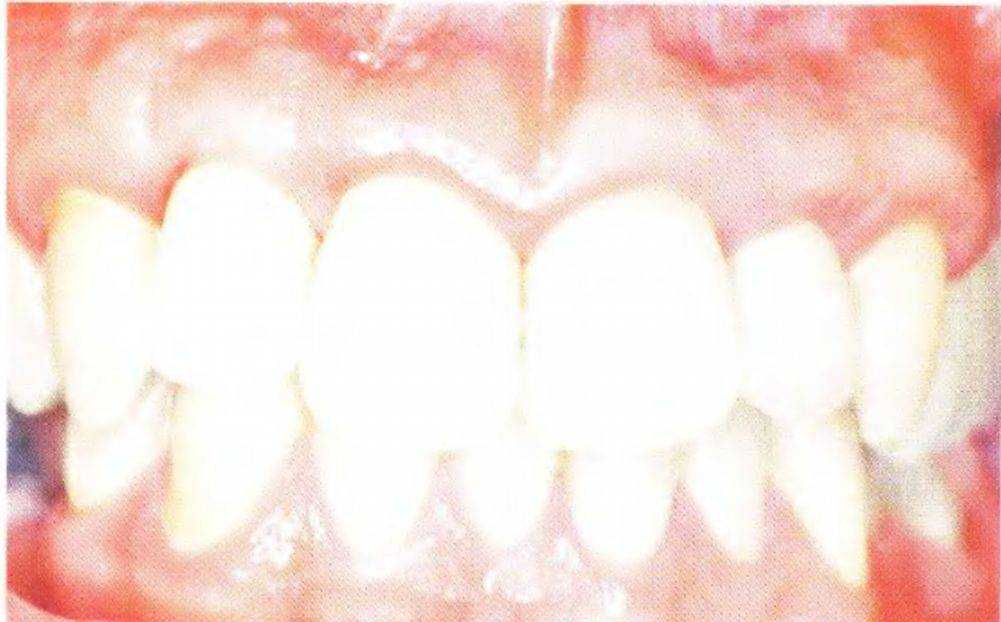

Рис. 3-39Ь. Клиническая картина со съемным частичным протезом

Рис. 3-39h. Окклюзионныи вид после ортодонтического лечения.

Рис. 3-39i. Клиническая картина в переднебоковой проекции